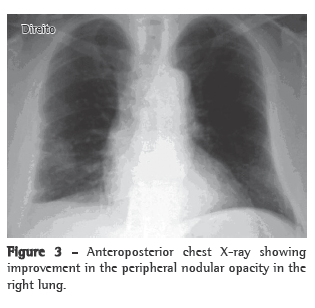

With treatment, the patient presented improvement of the clinical manifestations and the pulmonary alterations resolved (Figure 3).

Imaging studies showed an extensive unilateral nodular lesion. This finding is uncommon in WG and, therefore, there was diagnostic difficulty in view of the possibility of a malignant disease. What is expected in this type of vasculitis is pulmonary infiltration or bilateral multiple nodules, which can be accompanied by cavitations (in 50% of the cases).(8) The next step was then to resort to tomography-guided percutaneous biopsy, a procedure that has high sensitivity, specificity and accuracy, the last ranging from 84.5% to 90%, depending directly on the size of the lesion. The principal reason for requesting the procedure is to determine malignancy in solid pulmonary lesions.(9,10)